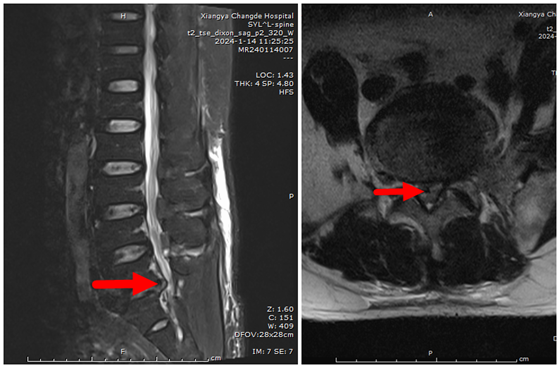

近日,湘雅常德医院骨科成功完成首例单侧双通道内镜下腰椎髓核切除术+椎管扩大减压术(简称“UBE”),帮助56岁王先生解决了腰腿疼痛的问题。此次UBE技术的开展填补了我院该项技术...